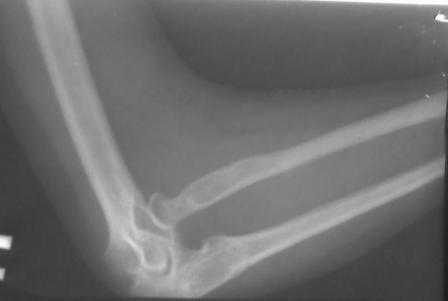

Уважаемые Коллеги! Добрый вечер! Обратилась девушка 18-лет, с жалобами на деформации обоих локтевых суставов, больна с рождения. Оба локтевых сустава в положении сгибания под углом 145гр., дальше разгибание нет за счет укороченных и натянутых м/тканей по передне-наружной поверхности л/сустава. Сгибание полное. но при сгибание предплечья супинируется а при разгибание пронируется,при фиксированным п/плечье ротационных движений нет.Со стороны костно-суставной системы других обл. я патологию не находил. В 2001 г. оперирована лев.рука в одном из центральном институте, со слов вывых был вправлен открыто и фиксация аппаратом Илизарова, после операции рука не сгибалась и ротационных движений не было, что очень ей мещало, после усиленных ЛФК наступило релюксация и движение стало лучше, т.е. как прежная. Фото и Р-снимки прилагается.

Снимки недостаточно информативны ( может быть не все сообщения пришли), рассматривать конфликт проксимального лучелоктевого сочленения невозможно без картинок дистального отдела. Глядя на представленные снимки и предъисторию открытого вправления с рецидивом вывиха, создается впечатление о диспропорции длины локтевой и лучевой костей, врожденном отсутствии аннулярной связи, удерживающей проксимальное лучелоктевое сочленение. Я бы посоветовал сделать снимки предплечья полной длины, включающих дистальное и

проксимальное л.л. сочленения и исходя из этого можно планировать вмешательство: как вариант при обнаружении диспропорции - укорачивающая

остеотомия луча с пластикой связки, если интраоперационно сохраняется тенденция к вывиху.